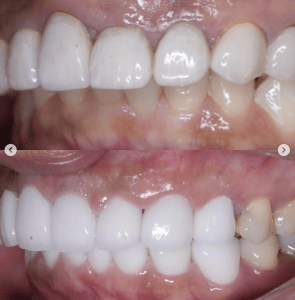

他院で実施したセラミック矯正の再治療を希望された患者様の症例です。

■色をもっと透明感のある白にしたい。

→当院自慢の一流技工士による最高品質ジルコニアセラミックにて透明感のある白へ

実際は写真でみるよりももっと透明感があります。

■前歯の歯の長さが違うのを治したい

→レーザーによる歯肉整形術で均等な歯の長さへ

■出っ歯に作られている前歯を引っ込めたい

→施術を担当した理事長の形成により、内側に入れるデザインにして洗練された口元へ。これによりEラインも整います。

■歪んだ歯並びを綺麗に

→施術を担当した理事長による形成、印象と技工士との連携により綺麗な歯並びへ

■タバコを吸ってた頃のヤニのついた黒くなってしまった歯茎が気になる

→レーザーによるメラニン色素除去でピンク色の歯茎に戻して若々しい印象へ